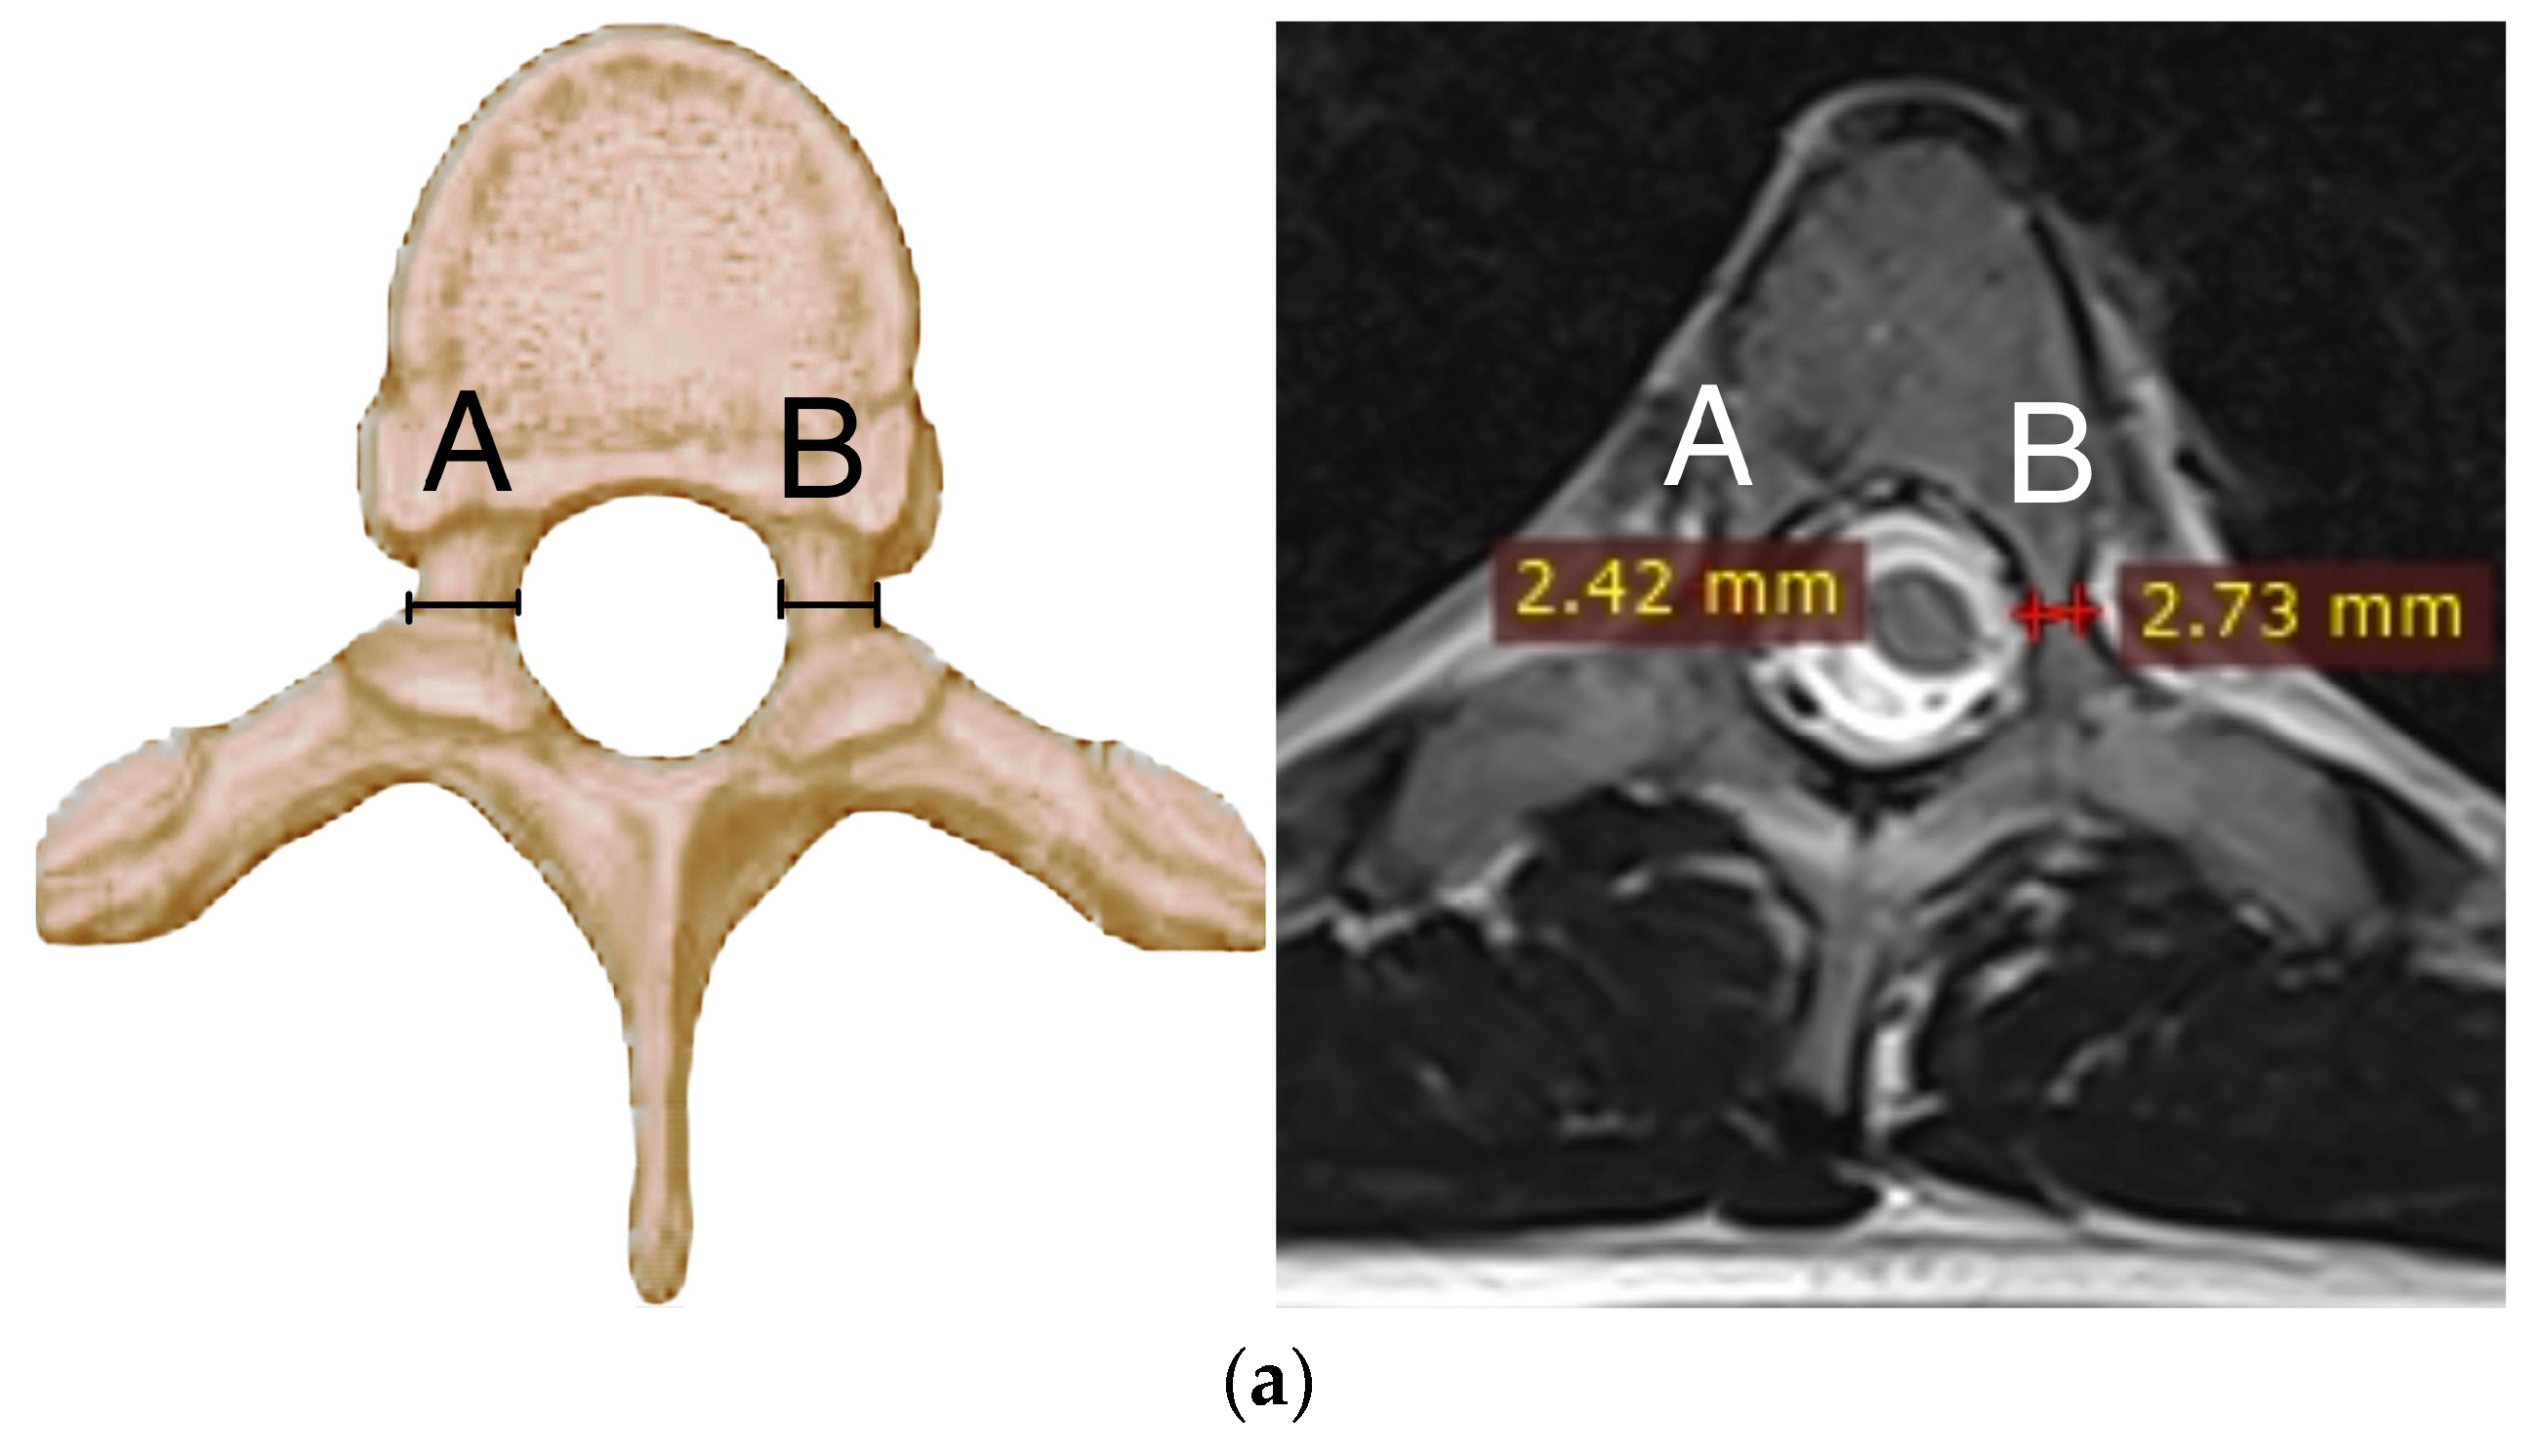

2.3. Radiographic Parameters